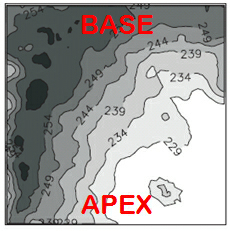

Electromechanical dysfunction in LQTS - image-based bio-physical modeling

We aim at elucidating how the impaired cardiac repolarization in LQTS affects mechanical function using magnetic resonance imaging methods to determine regional differences in contraction and relaxation velocities. Using these data on electrical and mechanical function, we aim at generating an electromechanical model of the LQTS heart. We aim at elucidating how the impaired cardiac repolarization in LQTS affects mechanical function using magnetic resonance imaging methods to determine regional differences in contraction and relaxation velocities. Using these data on electrical and mechanical function, we aim at generating an electromechanical model of the LQTS heart.